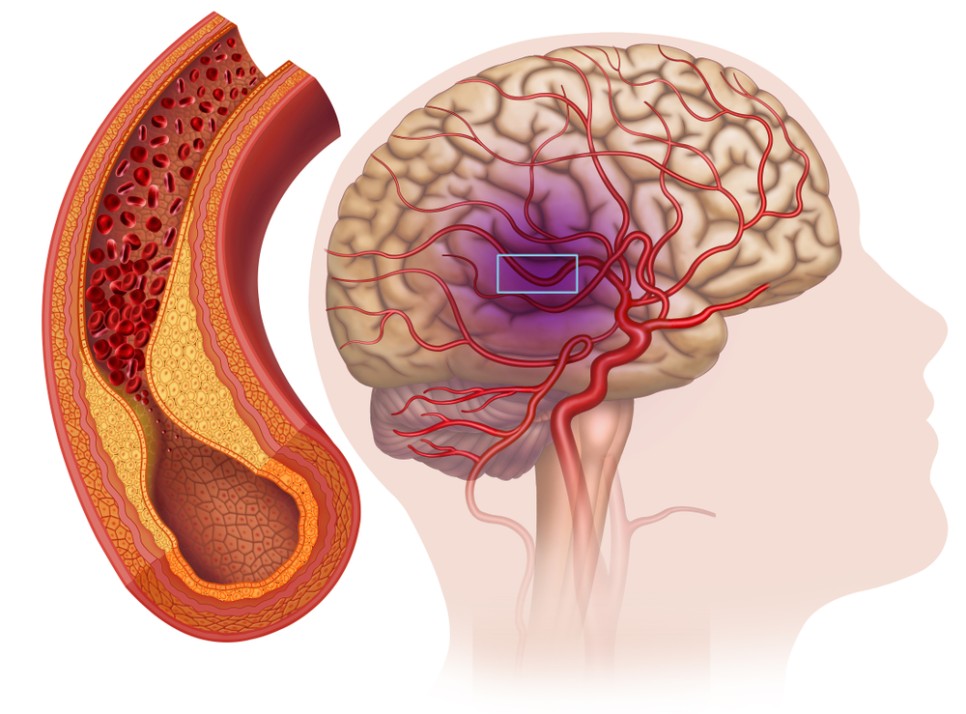

뇌로 가는 혈액의 80%를 보내는 목에 있는 중요한 혈관으로 경동맥의 동맥경화가 진행되면 뇌중풍의 발생 위험이 높아지기 때문입니다. 경동맥에 생긴 찌꺼기가 뇌 혈관으로 흘러 들어가서 뇌 혈관을 막을 확률이 높아집니다.

경동맥이 막히는 질환을 ‘경동맥 협착증’이라고 합니다. 허혈성 뇌중풍(뇌졸중) 원인의 30%를 차지할 정도로 우리 생활에 크게 다가온 경동맥 협착증.

뇌에 혈관이 막히거나 뇌경색에 의한 뇌기능 마비, 심한 경우 사망할 수도 있습니다.경동맥 협착증 치료